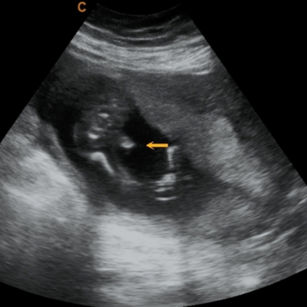

19 Weeks 1 Day Pregnant

Size: ~6 inches (15 cm), the size of a Heirloom Tomato

Skin developing layers; covered in lanugo (fine hair).

Baby may start moving vigorously—kicking, rolling, stretching.

Taste buds developing; baby can swallow amniotic fluid.

Hair on head continues growing.